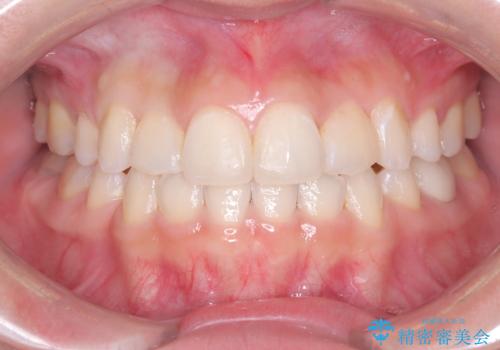

前歯の突出を防ぎながらガタつきを解消。上下左右4番抜歯による審美ワイヤー矯正

担当医 河口智英